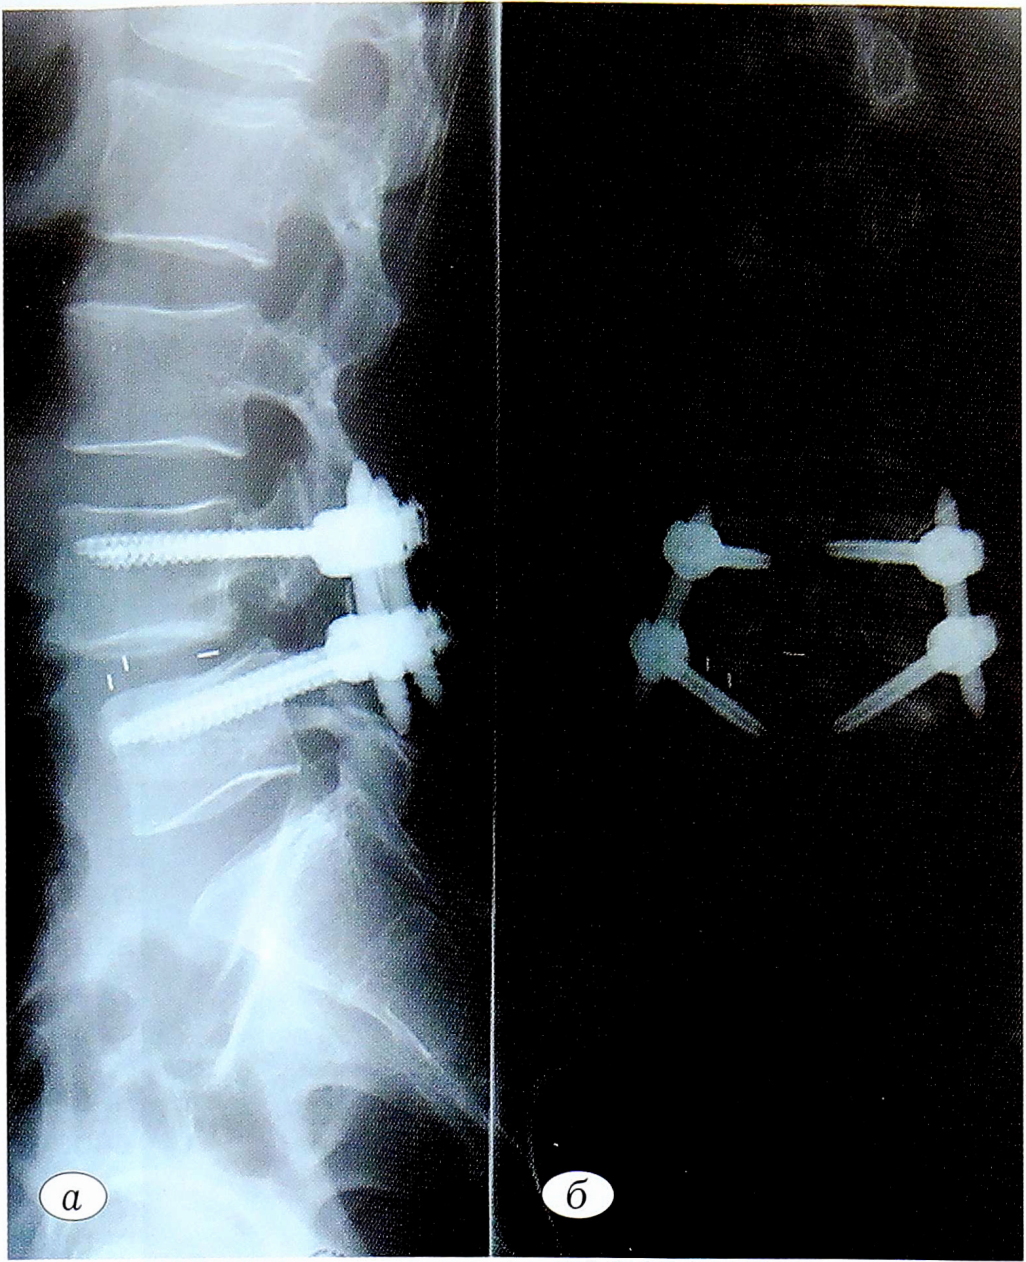

Пациент был активизирован на следующие сутки после операции. Данные поясничной спондилографии в прямой и боковой проекциях (рис. 4): состояние после межтелового спондилодеза с транспедикулярной фиксацией в сегменте LIV—LV, редукция антеспондилолистеза позвонка LV до I стадии. Положение элементов конструкции правильное, признаков миграции элементов конструкции не выявлено.

Рис. 4. Послеоперационная спондилография поясничного отдела позвоночника пациента Ш.: а — боковая проекция; б — прямая проекция.

Fig. 4. Postoperative spondylography of lumbar spine of the patient sh: a — lateral projection; b — direct projection.